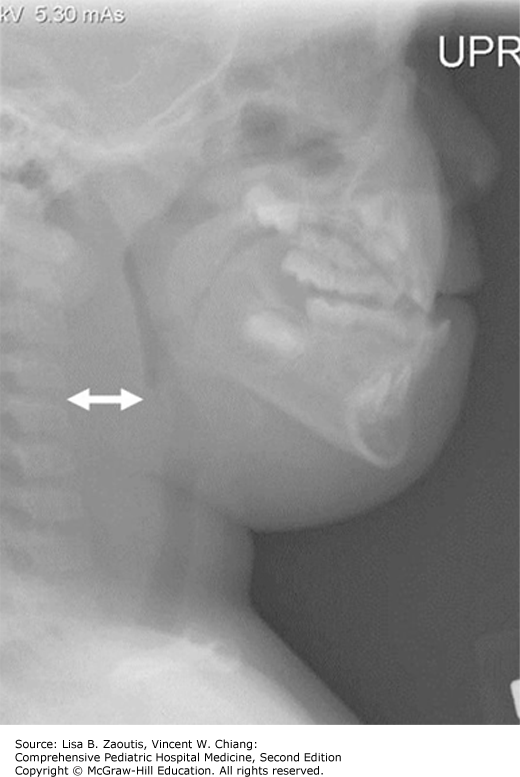

Answer: Retropharyngeal abscess. Enlarged retropharyngeal space secondary to soft tissue swelling anterior to the upper cervical bodies seen in a retropharyngeal abscess.

From: Zaoutis LB, Chiang VW. Comprehensive Pediatric Hospital Medicine, 2e; 2017 Available at: http://accesspediatrics.mhmedical.com/ViewLarge.aspx?figid=170329862  Accessed: February 13, 2018